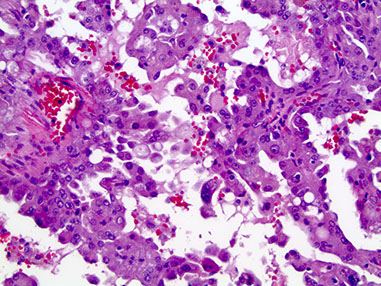

Mammary Analogue Secretory Carcinoma (MASC)

Tumor of the parotid c microcystic, papillary, and tubular patterns

- has a relation to acinic cell carcinoma and breast cancers, the genetics is mostly what makes it unique

- usually are slow growing lesions in the parotid of young males

- resembles secretory ca of the breast

IHC: (+) GCDFP-15, MUC1, BRST-2 and mammaglobin, CK, S100

- sometimes has (+) mucicarmine in intraluminal spaces

- negative HER2

Genetics: t(12;15)(p13;q25), ETV6-NTRK3 gene hybrid is diagnostic

MASC